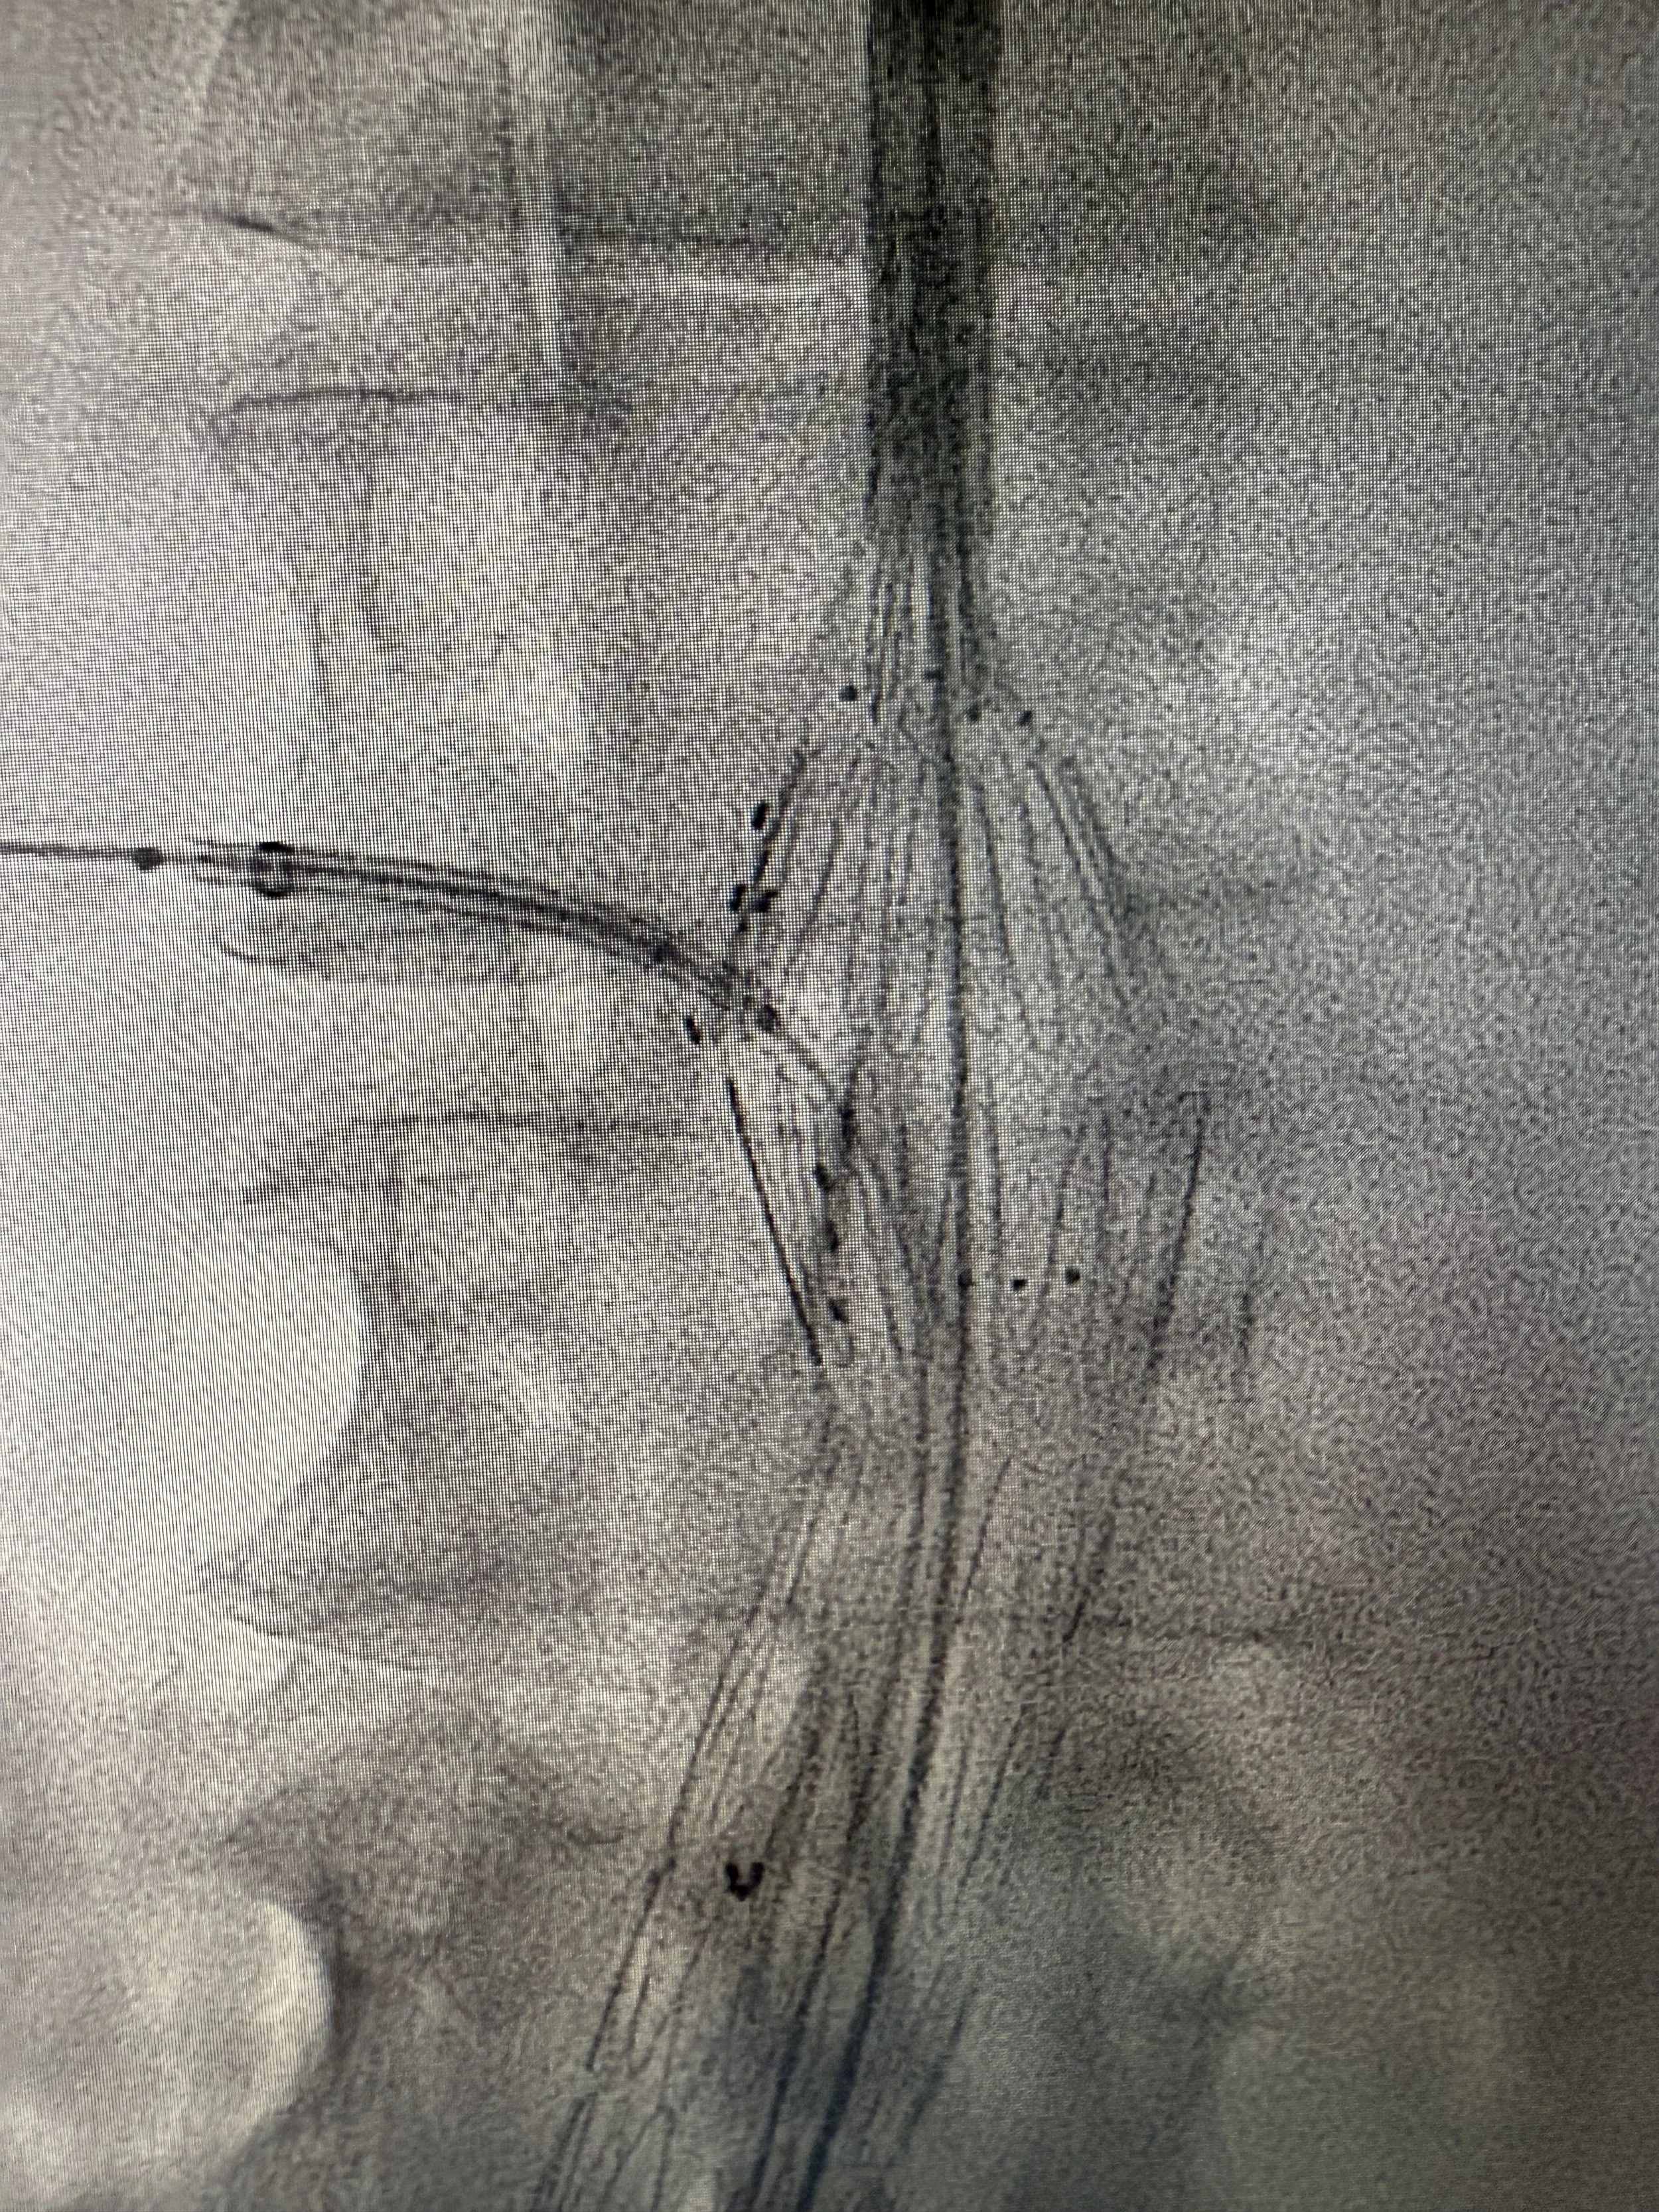

• Minimal-invasive Eingriffe bei der Aorta (EVAR, FEVAR, TEVAR)

Ich bin ein anerkannter Facharzt für Herz- und thorakale Gefässchirurgie sowie Chirurgie mit Schwerpunkt Aortenchirurgie & komplexer Gefässchirurgie. Mit umfassender internationaler Erfahrung, unter anderem als Consultant Vascular Surgeon am Guy’s and St. Thomas’ NHS Trust in London und als Chef de Clinique an der CHU Bichat-Claude Bernard in Paris, biete ich modernste gefässchirurgische Behandlungen auf höchstem Niveau. Meine Expertise umfasst minimal-invasive endovaskuläre Verfahren, komplexe Aortenchirurgie, Karotis-Chirurgie sowie venöse Eingriffe. Ich bin Mitglied der FMH und verfügt über Zusatzausbildungen wie Phlebologie (USGG) und Endovenöse thermische Ablation.